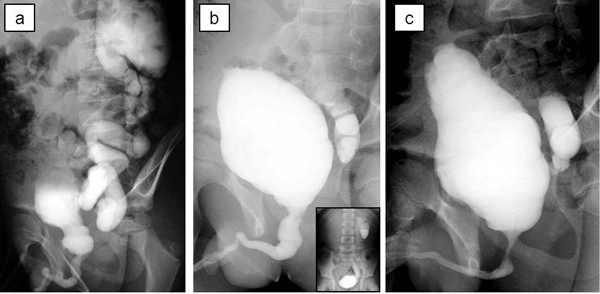

A 7-year-old boy was referred with febrile UTI in addition to severe bilateral hydroureteronephrosis on ultrasonography. He had no history of abnormal findings on prenatal ultrasonography. Voiding cystourethrography and diuretic renography revealed VURD syndrome (Fig. 3a). Subsequently, he underwent transurethral incision of the valves. The unilateral reflux remained unchanged on postoperative voiding cystourethrography (Fig. 3b). He underwent left nephroureterectomy at 9 year of age. At 10 years of age, the bladder compliance was 17 ml/cm H2O on video urodynamic study (Fig. 3c). After that, he developed recurrent UTIs and worsening dilatation of the contralateral upper urinary tract although he continued to take anticholinergic drugs. He required clean intermittent catheterization to control UTI and prevent deterioration of contralateral kidney caused by bladder dysfunction. Right SFU grade 4 hydroureteronephrosis improved to grade 2 after the start of clean intermittent catheterization. The estimated glomerular filtration rate was 81 ml/m/1.73 m2 at 11 year of age.

Figure 3: Voiding cystourethrography; (a) before transurethral incision of the valve, (b) before left nephroureterectomy, (c) 6 months after nephroureterectomy. Bladder trabeculation growing worse. |